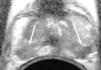

Los criterios utilizados en la RM para considerar que el tumor prostático tiene extensión extracapsular incluyen7,51 (fig. 8): protrusión focal irregular espiculada de la cápsula , pérdida de la hiposeñal normal de la cápsula, obliteración del ángulo rectoprostático, asimetría y afectación del plexo neurovascular y extensión del tumor a las vesículas seminales (tabla 3). La invasión de la vesícula seminal se demuestra por la presencia de hiposeñal en el seno de las vesículas51. Se ha demostrado útil la utilización de la secuencia de difusión como criterio de infiltración de la vesícula seminal46 (fig. 9). Para obtener la máxima eficacia en la estadificación del cáncer de próstata en RM es imprescindible utilizar una bobina endorrectal o multicanal de pelvis con el fin de obtener estudios de alta resolución de la pelvis11.

Diagnóstico y estadificación con examen único de RM. Varón de 63 años con PSA 6ng/ml y porcentaje de PSA libre: 7%, sin biopsias previas. A) Hipointensidad difusa del lóbulo periférico izquierdo (flecha). B) Hipointensidad de la raíz de las vesículas seminales sugestiva de infiltración (flecha), mostrando el mapa paramétrico CDA con color azul (flecha) indicativo de restricción de la difusión con valores <1,2×10−3mm2/s (C) (factor b: 1.000s/mm2). D) Hipointensidad sutil de la rama púbica derecha e hiperintensidad en la RMD que traduce restricción de la difusión (flecha) (E), en relación con metástasis.